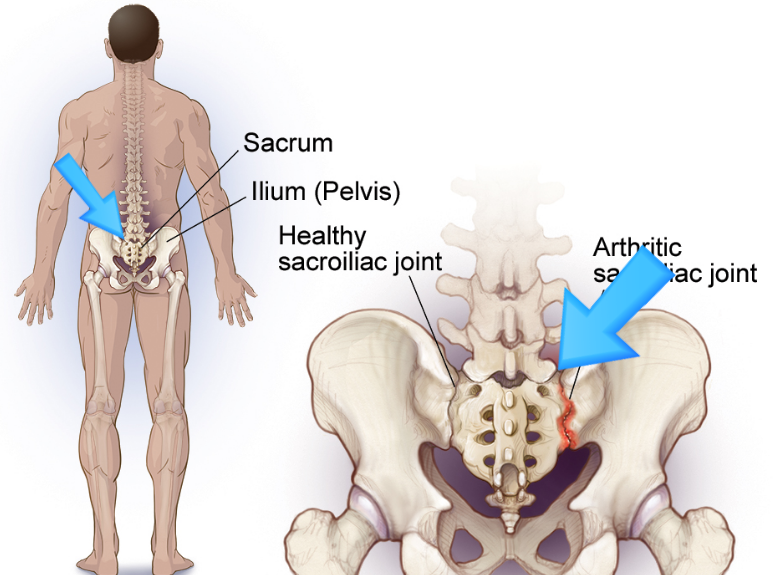

천장관절은 골반의 좌우측에 있는 골반뼈와 천골을 연결하는 관절입니다. 이 관절의 문제는 천골에 통증을 유발할 수 있습니다. 긴 척추를 골반까지 무너뜨려 안정성을 높여주는 관절입니다. 근육과 인대가 단단히 연결되어 있기 때문에 트러블이 잘 생기지 않습니다. 주변 인대가 손상되면 관절이 불안정해져 허리, 엉덩이, 허벅지 주변에 통증을 유발할 수 있다.